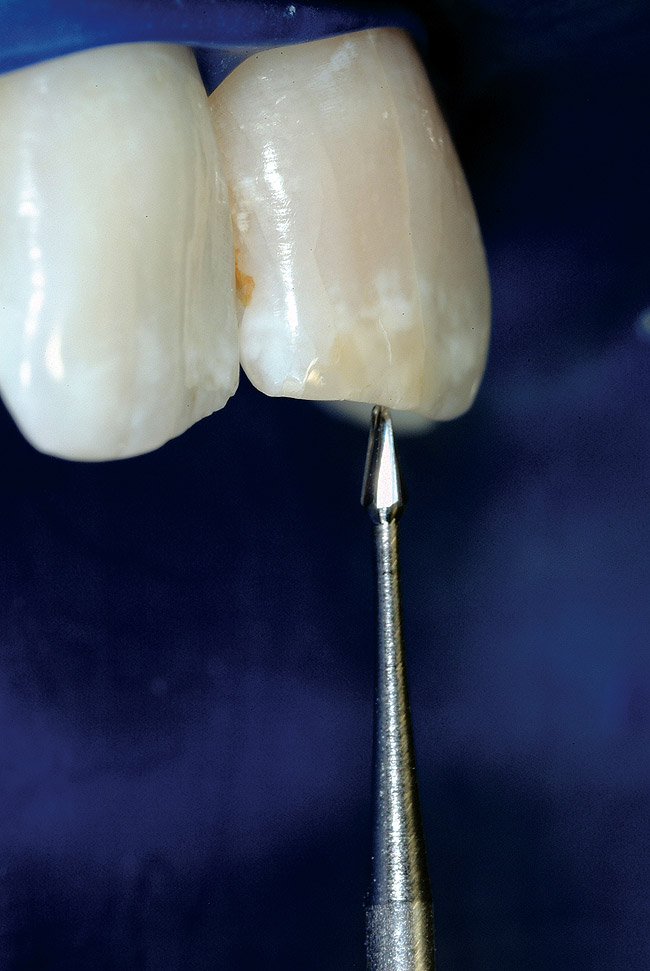

Round burs have long been the bur of choice when accessing beyond the initial cavosurface access of the tooth. Because of the rounded end, round burs seem safer than other burs. The round bur is also the most commonly used for accessing and subsequently exploring the calcified tooth in pursuit of a tiny wisp of pulp. Clinicians' bias toward this bur stems from a combination of factors, but is based mostly on habit. There is a universal misconception that round burs in a latch grip cut slowly and safely, but neither is the case. The radiograph in Figure 7 shows the dangerous gouging that is common with both a round bur and the parallel-sided tunnel that a round bur eventually creates. Rather, a conical shape is preferred. In the hands of a skilled clinician, the conical shape is possible to cut with a series of decreasing diameter round burs, but an uphill battle must be waged against the cutting action of round burs. With the advent of modern bur shapes, this exceedingly difficult and dangerous task is no longer necessary ( Figure 8 and Figure 9). Conical-shaped burs allow the clinician to work with the bur to create the ideal access shape. A secondary benefit is that one or two conical carbide burs can replace seven or more traditional burs, such as multiple round burs and Gates-Glidden burs, for instance.

Round burs have three inherent problems. Tip size is the first issue ( Figure 10). The tips are simply too big. The second problem is shape. The resultant irregular and parallel-sided cavity walls formed by a round bur work against the clinician when attempting to insert a hand file. When clinicians rummage around the calcified tooth with a round bur, it is common for the bur to become slightly misdirected. Then when inserting a file, it clunks into the bottom of the "well." The clinician has no choice but to continue to tunnel deeper and go back and forth, clunking hand files into the fruitless bottom and then burrowing deeper with round burs. In most cases, the wisp of pulp was higher up, like a trap door on the side wall ( Figure 11).

In the final analysis, round burs point cut in an endodontic access application, but planing is necessary. A new set of mental models based on vision is needed, along with a new set of instruments that are reflective of the task at hand and the desired shaping outcomes. The new vision-based mental model is "Look, Groom, Follow." The new burs are all rounded, ended tapers. Round burs tend to cut predictable shaping patterns that do not help the doctor or the tooth. 17